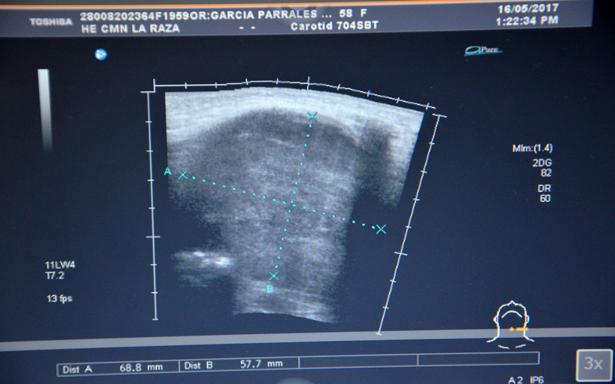

La endocrinóloga del Centro de Investigación y Docencia en Ciencias de la Salud (CIDOCS) de la UAS explicó que el hipotiroidismo es un trastorno en el cual la glándula tiroides no produce la cantidad suficiente de ciertas hormonas importantes.